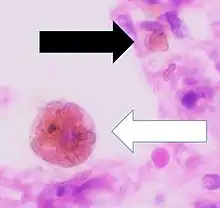

It is only found within cells (as opposed to circulating in blood) and appears to be a complex of ferritin, denatured ferritin and other material.[4][5] The iron within deposits of hemosiderin is very poorly available to supply iron when needed. Hemosiderin can be identified histologically with Perls' Prussian blue stain; iron in hemosiderin turns blue to black when exposed to potassium ferrocyanide.[6] In normal animals, hemosiderin deposits are small and commonly inapparent without special stains. Excessive accumulation of hemosiderin is usually detected within cells of the mononuclear phagocyte system (MPS) or occasionally within epithelial cells of the liver and kidney.

Cellular iron is found as either ferritin or hemosiderin. It is identified in cells by the Perls or Prussian blue reaction, in which ionic iron reacts with acid ferrocyanide to impart a blue color.<Wintrobe's Clinical Hematology>